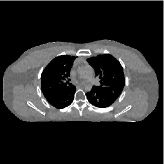

This section compares the reconstruction quality and runtime among the proposed MBIR method, PWLS-ST-, and other three MBIR methods, PWLS-EP, PWLS-DL, and PWLS-ST-. Table I shows that, for both 2D and 3D sparse-view CT reconstructions of the XCAT phantom, the proposed PWLS-ST- model outperforms PWLS-EP and PWLS-ST- in terms of RMSE. In addition, PWLS-ST- using a square transform (of size ) achieves lower RMSE than PWLS-DL using an overcomplete dictionary (of size ) for 2D sparse-view reconstructions. Fig. 3(a) and Fig. 4 show the reconstructed images for 2D and 3D phantom experiments, with different reconstruction models and different number of views. (See the corresponding error maps in the supplement.) The proposed PWLS-ST- consistently gives more accurate image reconstructions compared to other MBIR methods. Specifically, PWLS-ST- has smaller errors in the heart region (see zoom-ins in Fig. 3(a)) of 2D reconstructions than PWLS-DL and PWLS-ST-. In addition, compared to PWLS-ST-, PWLS-DL and PWLS-ST- have some ringing artifacts around the edges with high transition, e.g., edges between air and soft tissues. (See a comparison of profiles of PWLS-ST- and PWLS-ST- in the supplement.) In particular, PWLS-ST- and PWLS-DL give more visible ringing artifacts for 2D reconstruction from fewer views, and PWLS-ST- has these ringing artifacts for 3D reconstructions regardless of the number of views (see zoom-ins in Fig. 4). Table II reports runtimes of different MBIR methods in reconstructing the -views XCAT phantom scan. (FBPConvNet is a non-MBIR method and its runtime for processing a image is approximately one second with a TITAN Xp GPU.) While providing better reconstruction quality, the proposed Algorithm 1 of PWLS-ST- has shorter runtime compared to the algorithms of PWLS-DL and PWLS-ST- in Section III-A. Similar to the PWLS-EP algorithm, the reconstruction time of the PWLS-DL, PWLS-ST-, and PWLS-ST- algorithms can be further reduced by using ordered subsets [51].

| (b) 3D axial cone-beam CT experiments |